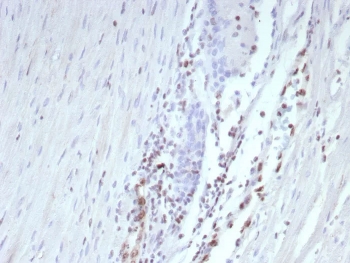

IHC staining of FFPE human prostate tissue with recombinant Transcriptional Regulator ERG antibody (clone ERG/9122R) at 2ug/ml. HIER: boil tissue sections in pH 9 10mM Tris with 1mM EDTA for 20 min and allow to cool before testing.